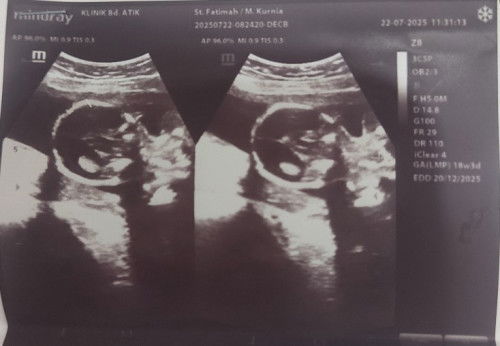

Hamil k 2 bnyak yg d rasa, pas 4 bln katanya Bayi nya ada cairan lebih d kepala. Coba yg prnah shari

diagnosa nya sudah tegak hydrops fetalis mam.? biasanya kalo ada kasus seperti ini suka di rujuk ke fetomaternal